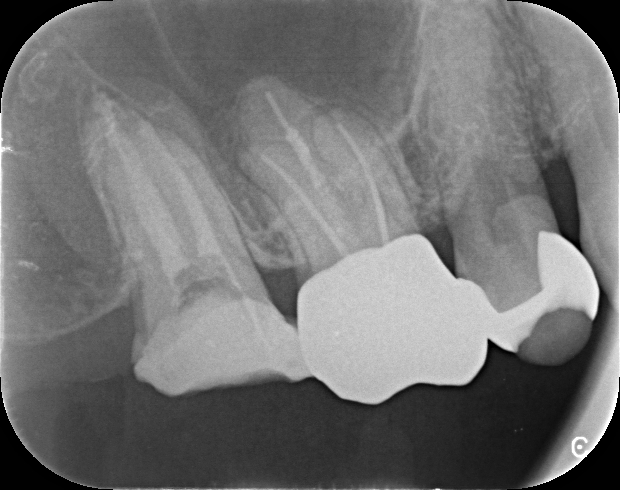

他院で抜歯宣告の歯を根管治療で保存

男性 2022年6月30日 公開

他院にて10回も治療された結果、ここまで根管治療をして改善が見られなかった場合は抜歯だと宣告された患者さんです。

しかし、当院で通法に従って根管内のガッタパーチャ(根管充填材)の除去および、マイクロスコープ(歯科用顕微鏡)を見ながら汚れを除去し、MTAで根管充填の処置を行ったところ、腫れも痛みも無くなり3回で治療終了になりました。

他院では、抜歯になった場合はインプラントだと言われていたそうで、インプラントにならずにすんで良かったと患者さんは喜んでおられました。